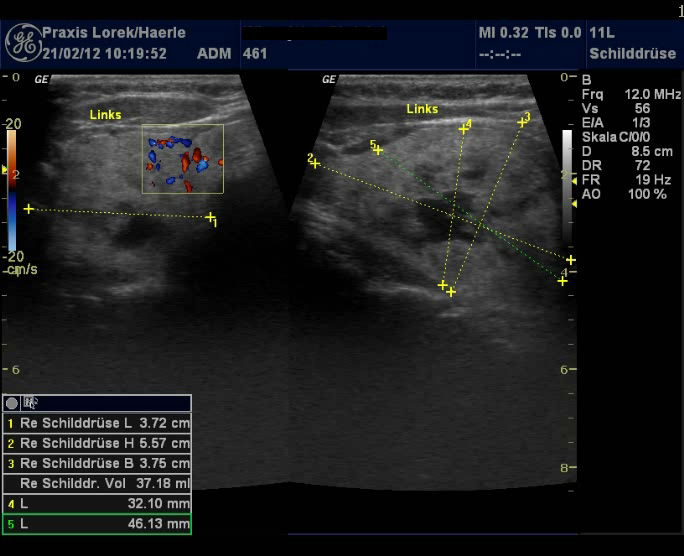

| Abb. 9 und 10: Ebenfalls

inhomogener Knoten wie bei Abb. 7 und 8, der Farbdoppler gibt eine

verstärkte Durchblutung an und lässt zwischen zystischen

Knoten-Strukturen und Gefäßen differenzieren. Tirads 4b.

67-jährige Patientin mit ebenfalls warmem Knoten unter supprimierender

Behandlung mit L-Thyroxin. |